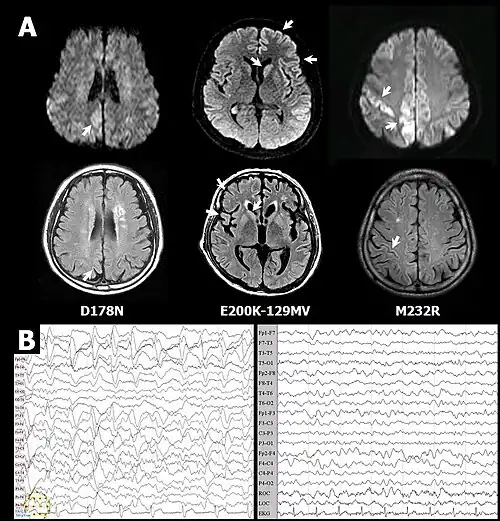

- ↑ Choi B.Y., Kim S.Y., Seo S.Y., An S.S., Kim S., Park S.E., Lee S.H., Choi Y.J., Kim S.J., Kim C.K., Park J.S., Ju Y.R. Mutations at codons 178, 200-129, and 232 contributed to the inherited prion diseases in Korean patients (англ.) // BMC Infect. Dis. : journal. — 2009. — Vol. 9. — P. 132. — doi:10.1186/1471-2334-9-132. — PMID 19698114. — PMC 2749045. Архивировано 28 сентября 2013 года.